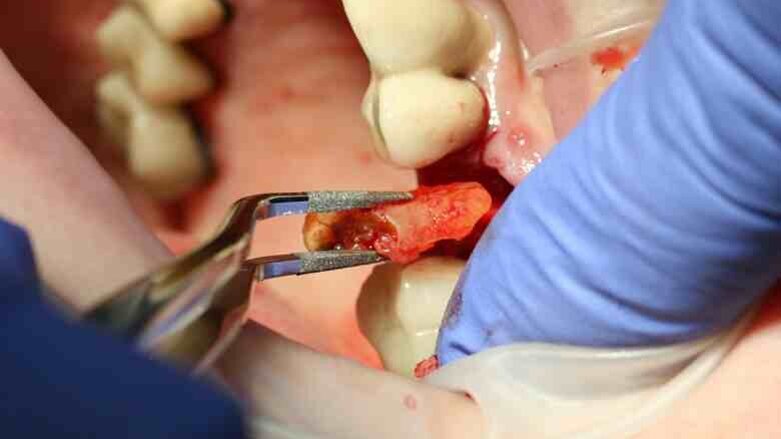

Fig. 8: The root could be lifted out with diamond-coated tweezers.

Luxator P4, with its extremely sharp dual-edge blade, was used at the beginning, followed by Luxator P1 once more space had been created. Although the blades of these sophisticated instruments are reinforced with a titanium coating, they should only be used to cut the periodontal ligament and never to elevate the tooth.

When the extraction had been completed, the alveolus was scraped and thoroughly flushed clean with physiological saline solution to prevent infection.